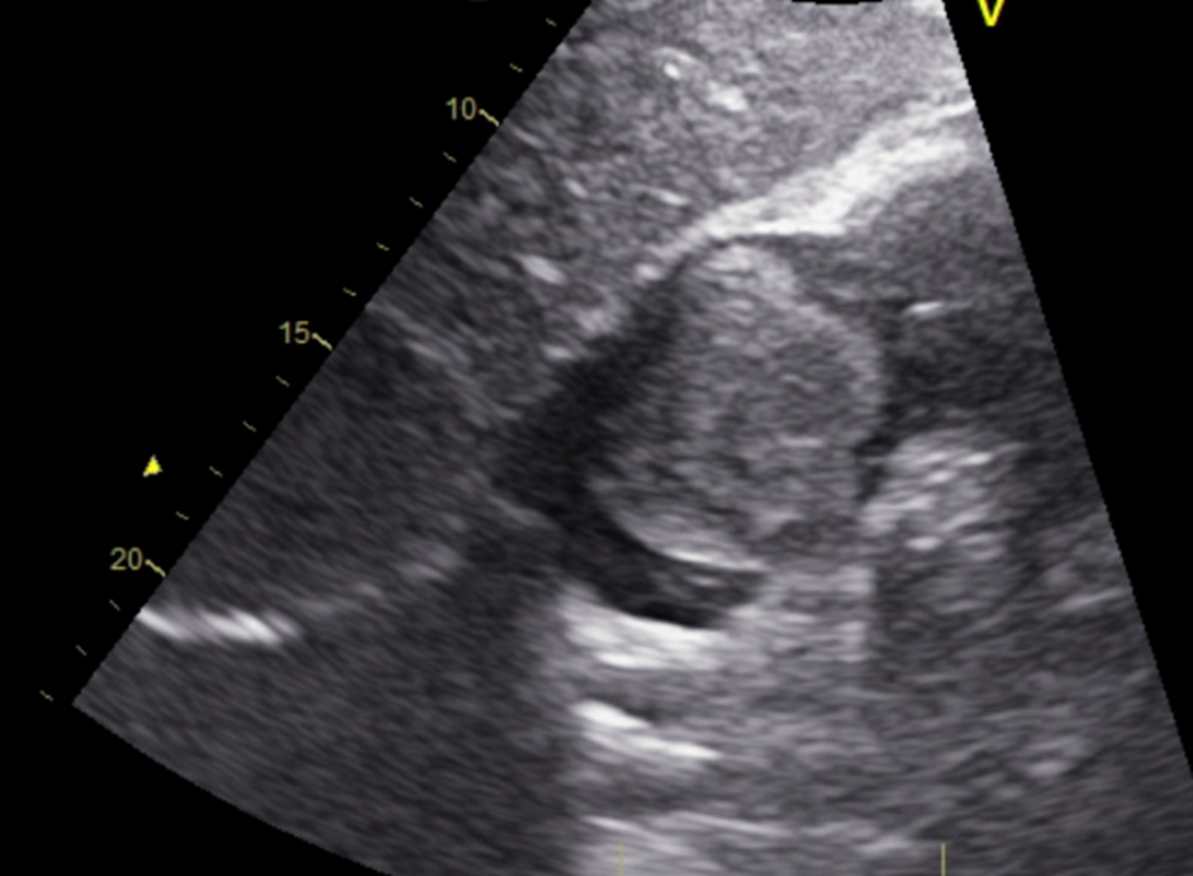

Primary Ventricular Palliation in Hypoplastic Left Heart Syndrome: A Case Report

Giovana Ferreira Vaz, Marcos Barbosa Guimarães Carvalho, Maria Eduarda Santos Gomes , João Vitor Mendes da Silveira, Leonardo Sardinha de Paula, Mirna de Sousa , Viviane Soares

bjcr182